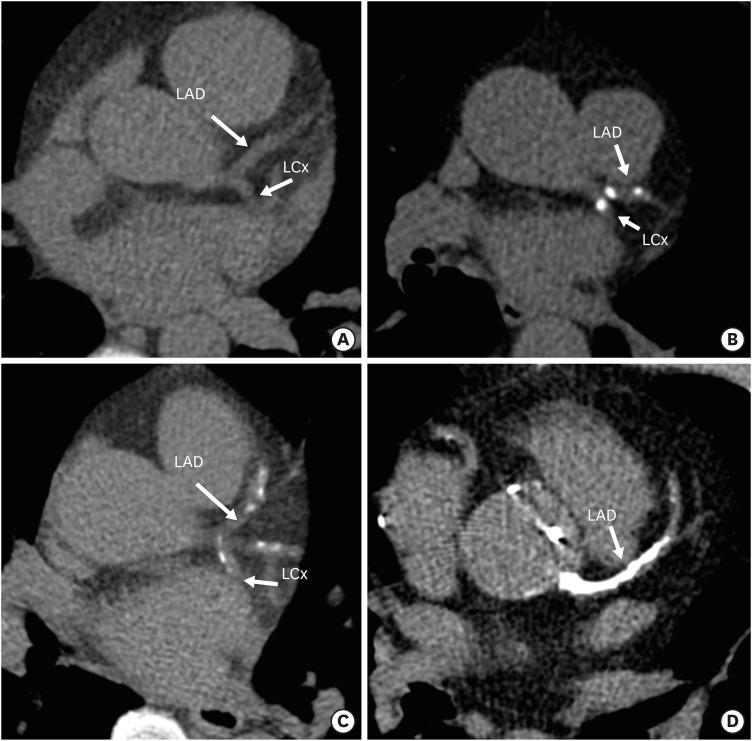

The Coronary Artery Calcium Data and Reporting System (CAC-DRS) is a standardized reporting method for calcium scoring on computed tomography. CAC-DRS is applied on a per-patient basis and represents the total calcium score with the number of vessels involved. There are 4 risk categories ranging from CAC-DRS 0 to CAC-DRS 3. CAC-DRS also provides risk prediction and treatment recommendations for each category. The main strengths of CAC-DRS include a detailed and meaningful representation of CAC, improved communication between physicians, risk stratification, appropriate treatment recommendations, and uniform data collection, which provides a framework for education and research. The major limitations of CAC-DRS include a few missing components, an overly simple visual approach without any standard reference, and treatment recommendations lacking a basis in clinical trials. This consistent yet straightforward method has the potential to systemize CAC scoring in both gated and non-gated scans.

冠状动脉钙化数据与报告系统(CAC-DRS)是一种用于计算机断层扫描中钙化评分的标准化报告方法。CAC-DRS是针对每位患者应用的,代表累及血管数量的总钙化评分。有4个风险类别,范围从CAC-DRS 0到CAC-DRS 3。CAC-DRS还为每个类别提供风险预测和治疗建议。CAC-DRS的主要优势包括对冠状动脉钙化进行详细且有意义的呈现、改善医生之间的沟通、风险分层、恰当的治疗建议以及统一的数据收集,这为教育和研究提供了一个框架。CAC-DRS的主要局限性包括一些缺失的部分、过于简单的视觉方法且没有任何标准参考,以及缺乏临床试验依据的治疗建议。这种一致且直接的方法有可能使门控和非门控扫描中的冠状动脉钙化评分系统化。